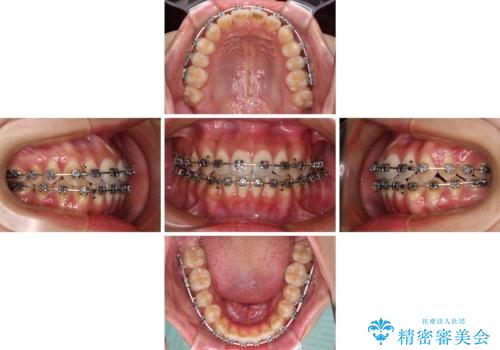

受け口と開咬を急速拡大装置とワイヤー装置で改善

- メタルブラケット

- 1年3ヶ月

上顎歯列が狭窄していたため、急速拡大装置により上顎骨を側方に拡大し、その後ワイヤー装置にて矯正治療を行うこととしました。

舌の突出癖が開咬の原因であったので、改善のための舌トレーニングを行っていただきました。

舌トレーニングは後戻りにも大きく影響するため、とても重要なトレーニングです。